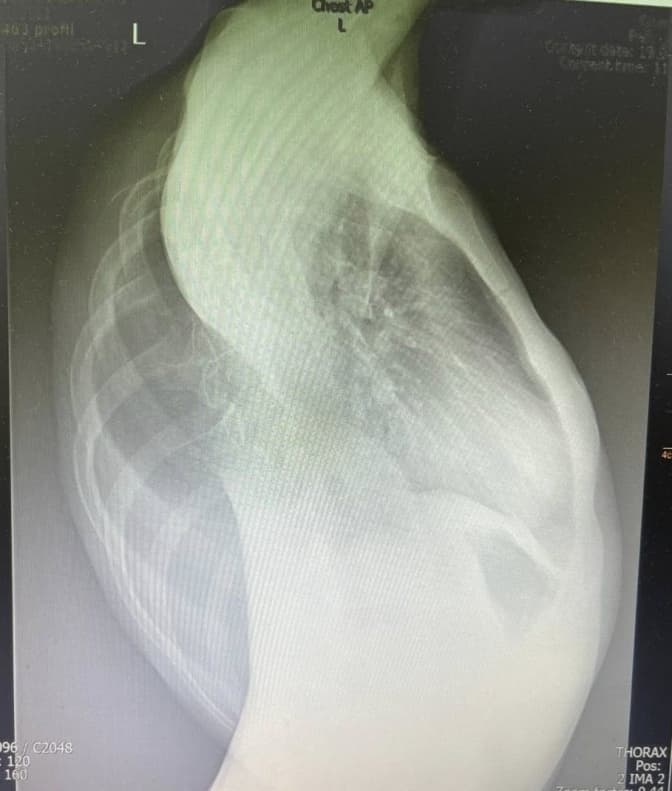

У Центр дитячої медицини лікарні «Охматдит» потрапила 13-річна дівчинка з пневмонією. Важке дихання, слабкість, погані результати обстежень – в такому стані була пацієнтка. Про це повідомили в «Охматдиті» .

На УЗД легенів лікарі помітили велике пневмонічне вогнище. Кілька разів обстеження повторювали, і хоча дитина почувалася краще, результати не змінювались. Ультразвук показував ті ж самі зміни без позитивної динаміки. І це при покращенні показників крові.

Було прийнято рішення зробити комп’ютерну томографію. Це стало переломним моментом у цій історії. Діагноз: глибока деформація грудної клітки зі сколіозом.

Хребет настільки викривлений, що здавлює одну з легенів. Це спричинило не просто пневмонію, а вже хронічні фіброзні зміни в легеневій тканині – тобто незворотні наслідки.

«Зі слів мами, викривлення почало розвиватися у 10 років. Але ми, лікарі, розуміємо – процес почався раніше. Просто тоді ще не було видимих симптомів. Складність випадку вимагала мультидисциплінарного підходу», - прокоментувала педіатр-алерголог Центру Руслана Проць.

Фото: Охматдит